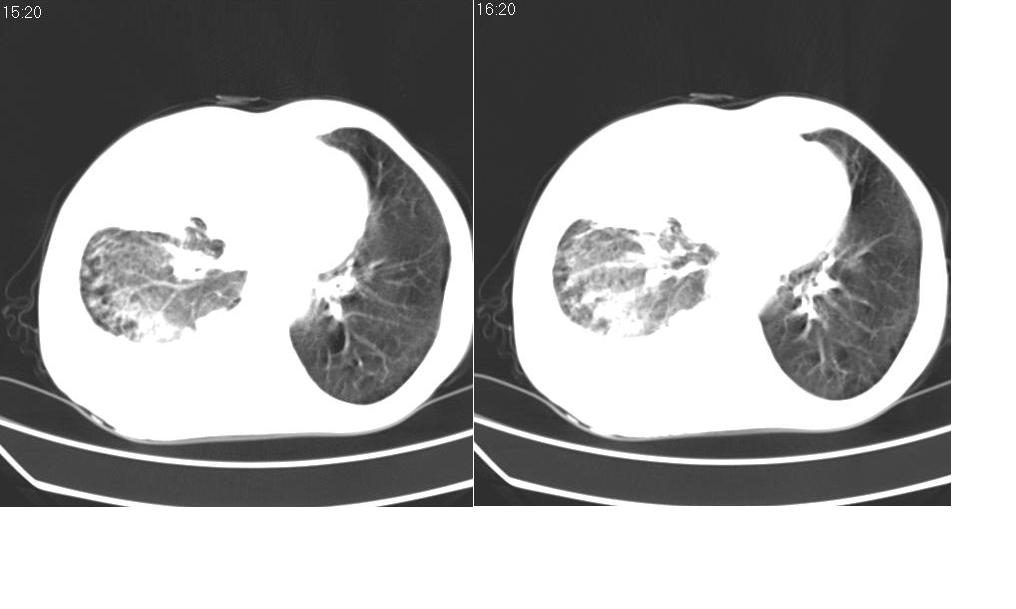

以下是引用zsl6918在2008-5-3 19:53:00的发言:[br]右肺中心型肺癌并纵隔淋巴结转移,胸膜转移,右肺癌性淋巴管炎。

以下是引用liuyue在2008-5-3 20:49:00的发言:[br]1.右侧中心型肺癌伴双肺转移瘤、纵隔淋巴结转移、右侧胸腔积液(侵及胸膜所致可能性大)。[br]2.右肺阻塞性肺炎,癌性淋巴管炎不除外。

以下是引用mzh123在2008-5-3 21:12:00的发言:[br]本人持有不同观点[br]1、右肺似有团块表现,但只有一个层面,所以本人认为还是以片为主,所以不能首先考虑肿瘤[br]2、右肺普遍成纤维化改变 并伴有片状炎症改变,和癌性淋巴管炎表现不同[br]3、所以本人认为是间质纤维化伴感染可能大 及胸腔积液